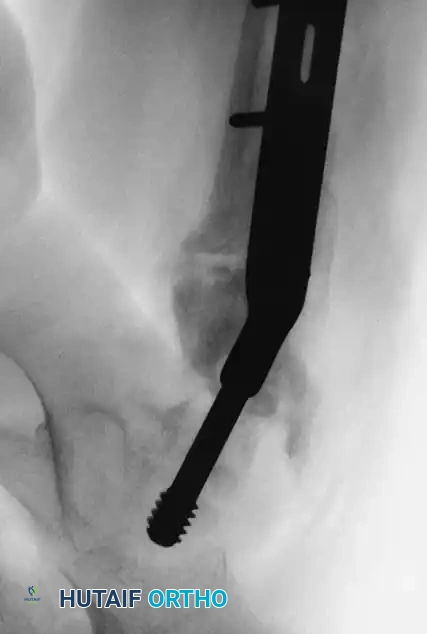

- Technique: Utilize a pediatric dynamic hip screw (DHS) or a cannulated screw with an attached side plate. This converts shear forces into compressive forces and rigidly maintains the neck-shaft angle.

Fig. 14: Displaced Type III cervicotrochanteric fracture prior to intervention.

Fig. 15: Intraoperative reduction of the Type III fracture.

Fig. 16: Final fixation utilizing a cannulated screw and attached side plate to neutralize shear forces.